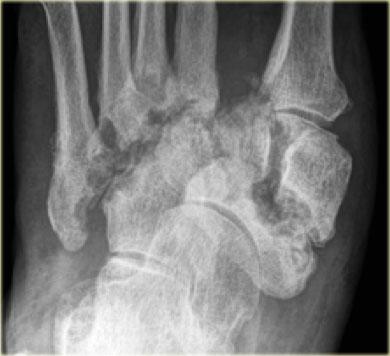

Đây là hình chụp X-quang của một bệnh nhân bị bệnh thần kinh do đái tháo đường và bàn chân đỏ nóng.

Trong giai đoạn cấp tính, hình chụp X-quang có thể bình thường và không thể loại trừ chẩn đoán bệnh xương khớp thần kinh Charcot cấp tính.

Trong vòng 4 tháng có sự giảm dần độ nghiêng xương gót với biến dạng ngựa tại khớp cổ chân.

Có sự phá hủy khớp cổ bàn chân với biến dạng bàn chân đế cong điển hình.

Bony debris is seen on the dorsal aspect of the foot.